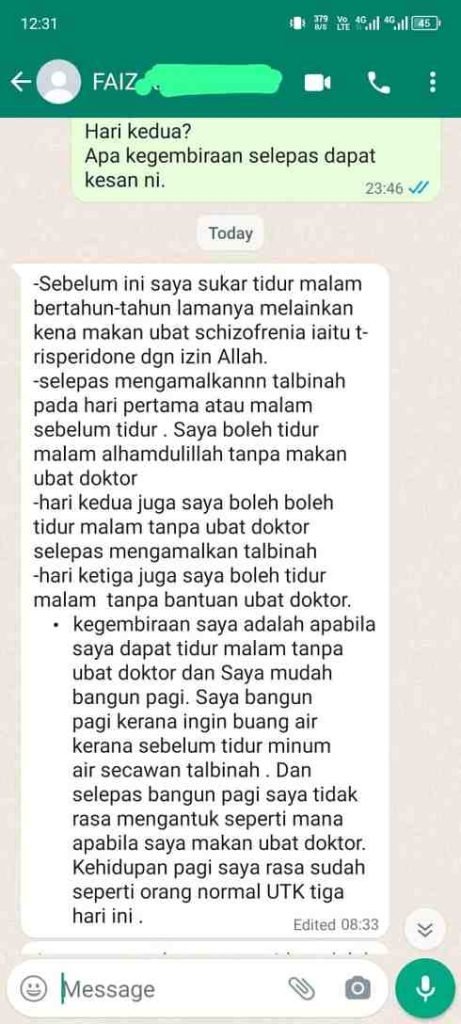

Lihat salah seorang pengguna kami yang anxiety dan depression.

Disangkakan sihir sampai kelar tangan dan kerap maki hamun, tetapi alhamdulillah dengan ikhtiar Talbinah semakin baik seawal 3 hari.

"Boleh tidur malam tanpa makan ubat hospital, ada schizo, dan mudah bangun"